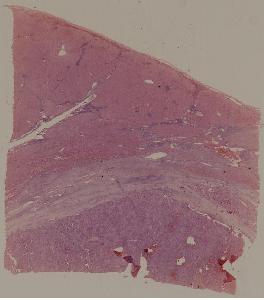

49. syphilitic aortitis

50. Labar pneumonia

51. Carnification of the lung

52. Lobular pneumonia

57. Carcinoma of the lung

59. Chronic atrophic gastritis

60. Gastric ulcer

61. Gastric adenocarcinoma(Mucinous adenocarcinoma of the stamoch)

62. Acute viral hepatitis (common type)

63.Chronic active viral hepatitis

64. Acute fulminant viral hepatitis

65. Subacute fulminant viral hepatitis

66. Active nodular cirrhosis of the liver

67. Inactive nodular cirrhosis of the liver

68. Biliary fibrosis

69. Hepatocellular carcinoma

72. Membranous glomerulonephritis

73. Acute glomerulonephritis

74. Crescentic glomerulonephritis

75. Chronic glomerulonephritis